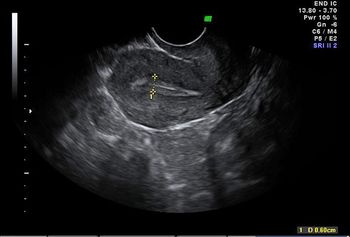

A 24-year-old pregnant patient presented with lower abdominal pain.